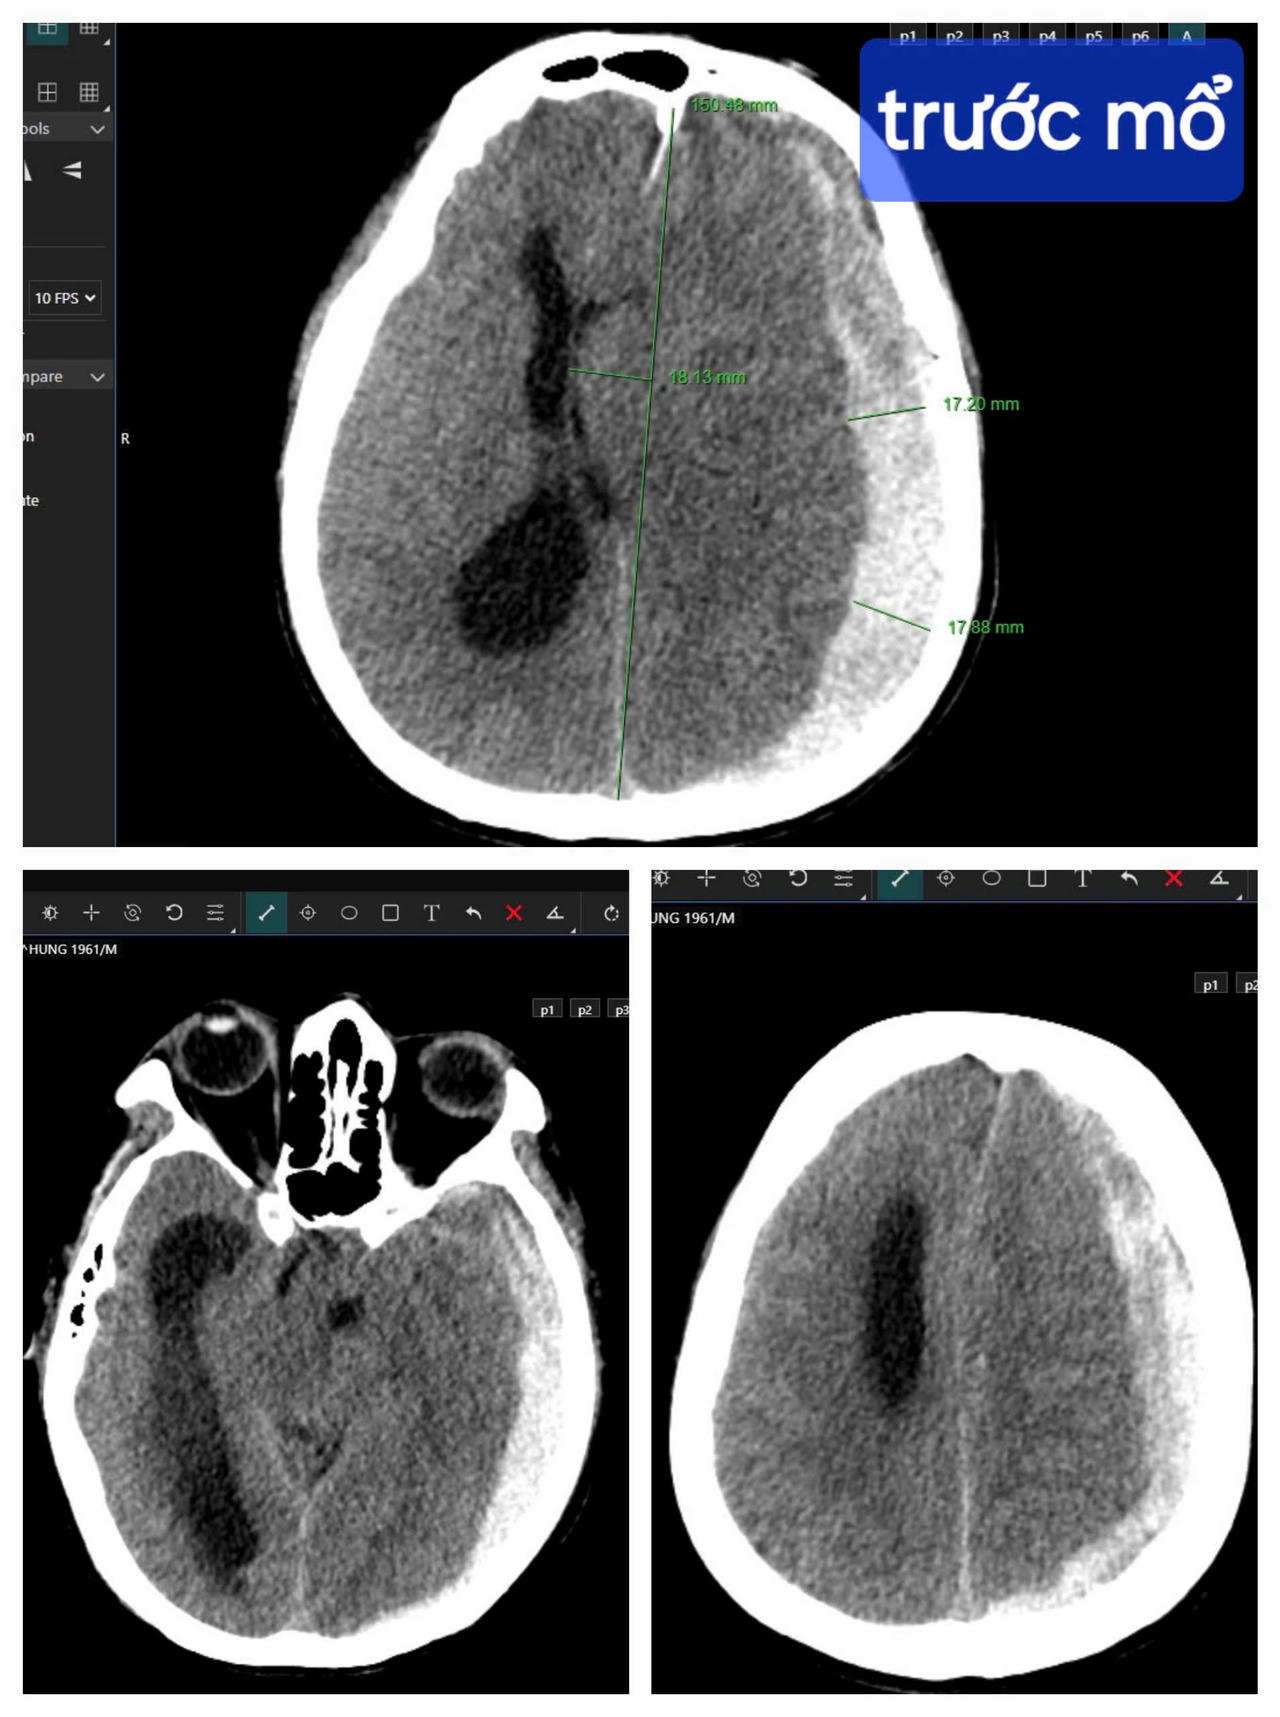

Kết quả chụp CT cho thấy bệnh nhân bị tụ máu dưới màng cứng bán cầu não trái, thoát vị qua liềm đại não sang phải. |

Trong tình huống khẩn cấp này, sự sống của bệnh nhân rất mong manh, bị tụ máu dưới màng cứng bán cầu não trái, thoát vị qua liềm đại não sang phải, bác sĩ phải chạy đua cùng thời gian, giành lại sự sống cho bệnh nhân từ tay “tử thần”.